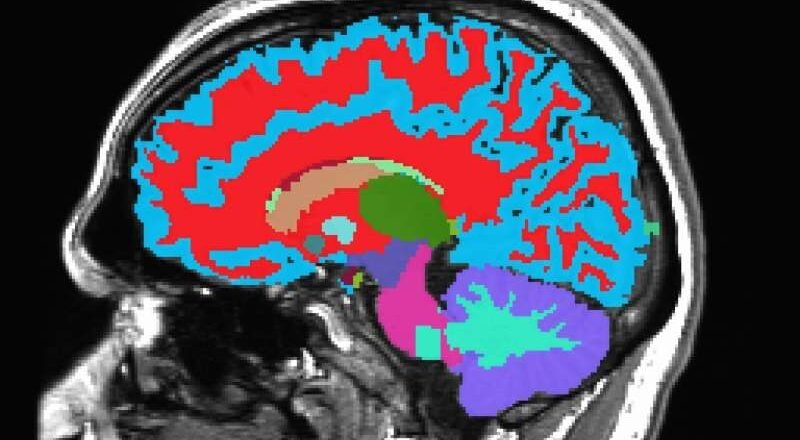

Las neuronas queman el azúcar de forma diferente: un descubrimiento ofrece una nueva esperanza para combatir la neurodegeneración

Un nuevo estudio realizado por científicos del Instituto Buck para la Investigación del Envejecimiento ha revelado un factor sorprendente en la lucha contra el Alzheimer y otras formas de demencia: el metabolismo cerebral del azúcar. Publicado en Nature Metabolism , la investigación revela cómo la descomposición del glucógeno (una forma almacenada de glucosa) en las neuronas puede proteger al cerebro de la acumulación de proteínas tóxicas y la degeneración.

El glucógeno se considera generalmente una fuente de energía de reserva almacenada en el hígado y los músculos. Si bien también existen pequeñas cantidades en el cerebro, en particular en las células de sostén llamadas astrocitos, su papel en las neur...